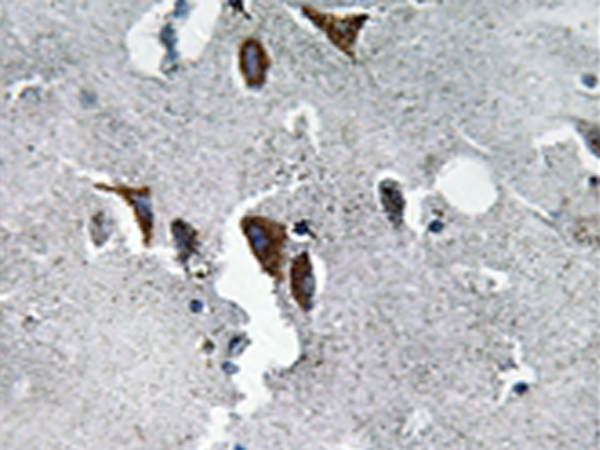

IHC positive control: |

Human brain tissue |